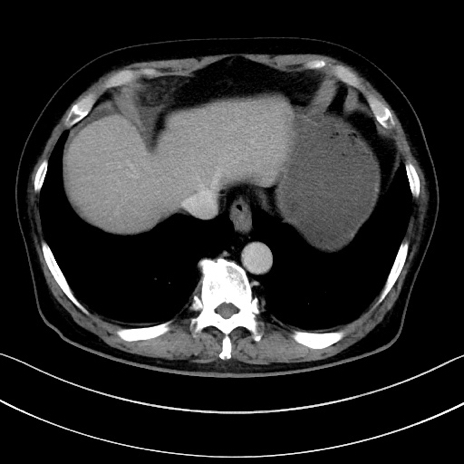

症例15(横断像)

【症例】70歳代男性

【主訴】腹痛

【現病歴】今朝から腹痛あり。全体的に痛い。特に左上の方。排ガスが今日はない。冷や汗が出る。

【既往歴】直腸癌術後

【身体所見】左側腹部〜上腹部に圧痛あり。腹膜刺激症状明らかなではない。軽度反跳痛。左下腹部に術後瘢痕あり。

【データ】WBC 7700、CRP 0.02